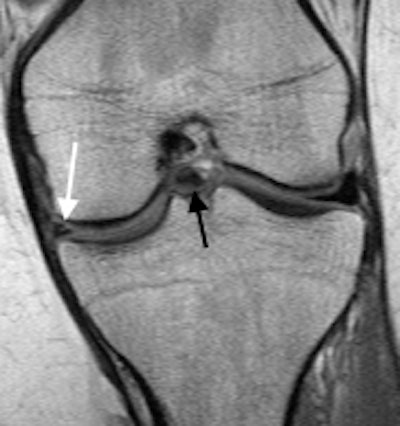

Distal rupture of the medial collateral ligament (arrow) on coronal short-tau inversion recovery of a 15-year-old boy. All images courtesy of Drs. Jacob Jaremko and Zachary Guenther.Along with colleagues from Ghent University Hospital in Belgium and Mater Misericordiae University Hospital in Dublin, he has shared his experiences of imaging of ACL tears in an article in Insights into Imaging, posted online on 9 May. The authors are concerned that insufficient attention is given to children and adolescent injuries.

Left: Bucket-handle tear of the medial meniscus in a 16-year-old girl. Coronal proton-density image demonstrates irregular, torn, medial meniscal body that is smaller than normal (white arrow), and the flipped portion of the medial meniscus that appears as an unexpected low signal structure below the posterior cruciate ligament in the intercondylar region. Right: Femoral condyle impaction fracture in a 15-year-old girl. Sagittal proton-density image shows cortical depression (arrow) with surrounding edema. Note the associated complex tear of the posterior horn of the lateral meniscus.In younger patients, the normal ACL can appear quite attenuated, and a recently torn ACL is usually visibly thickened and edematous, and a thin and appropriately oriented ligament without edema is likely intact, they stated. In the last 110 cases at the University of Alberta, 7/48 (15%) read by musculoskeletal radiologists and 26/62 (42%) read by pediatric radiologists were initially reported as high-grade partial-thickness ACL tears, while at later surgery all but one of these tears (99%) was described as complete.